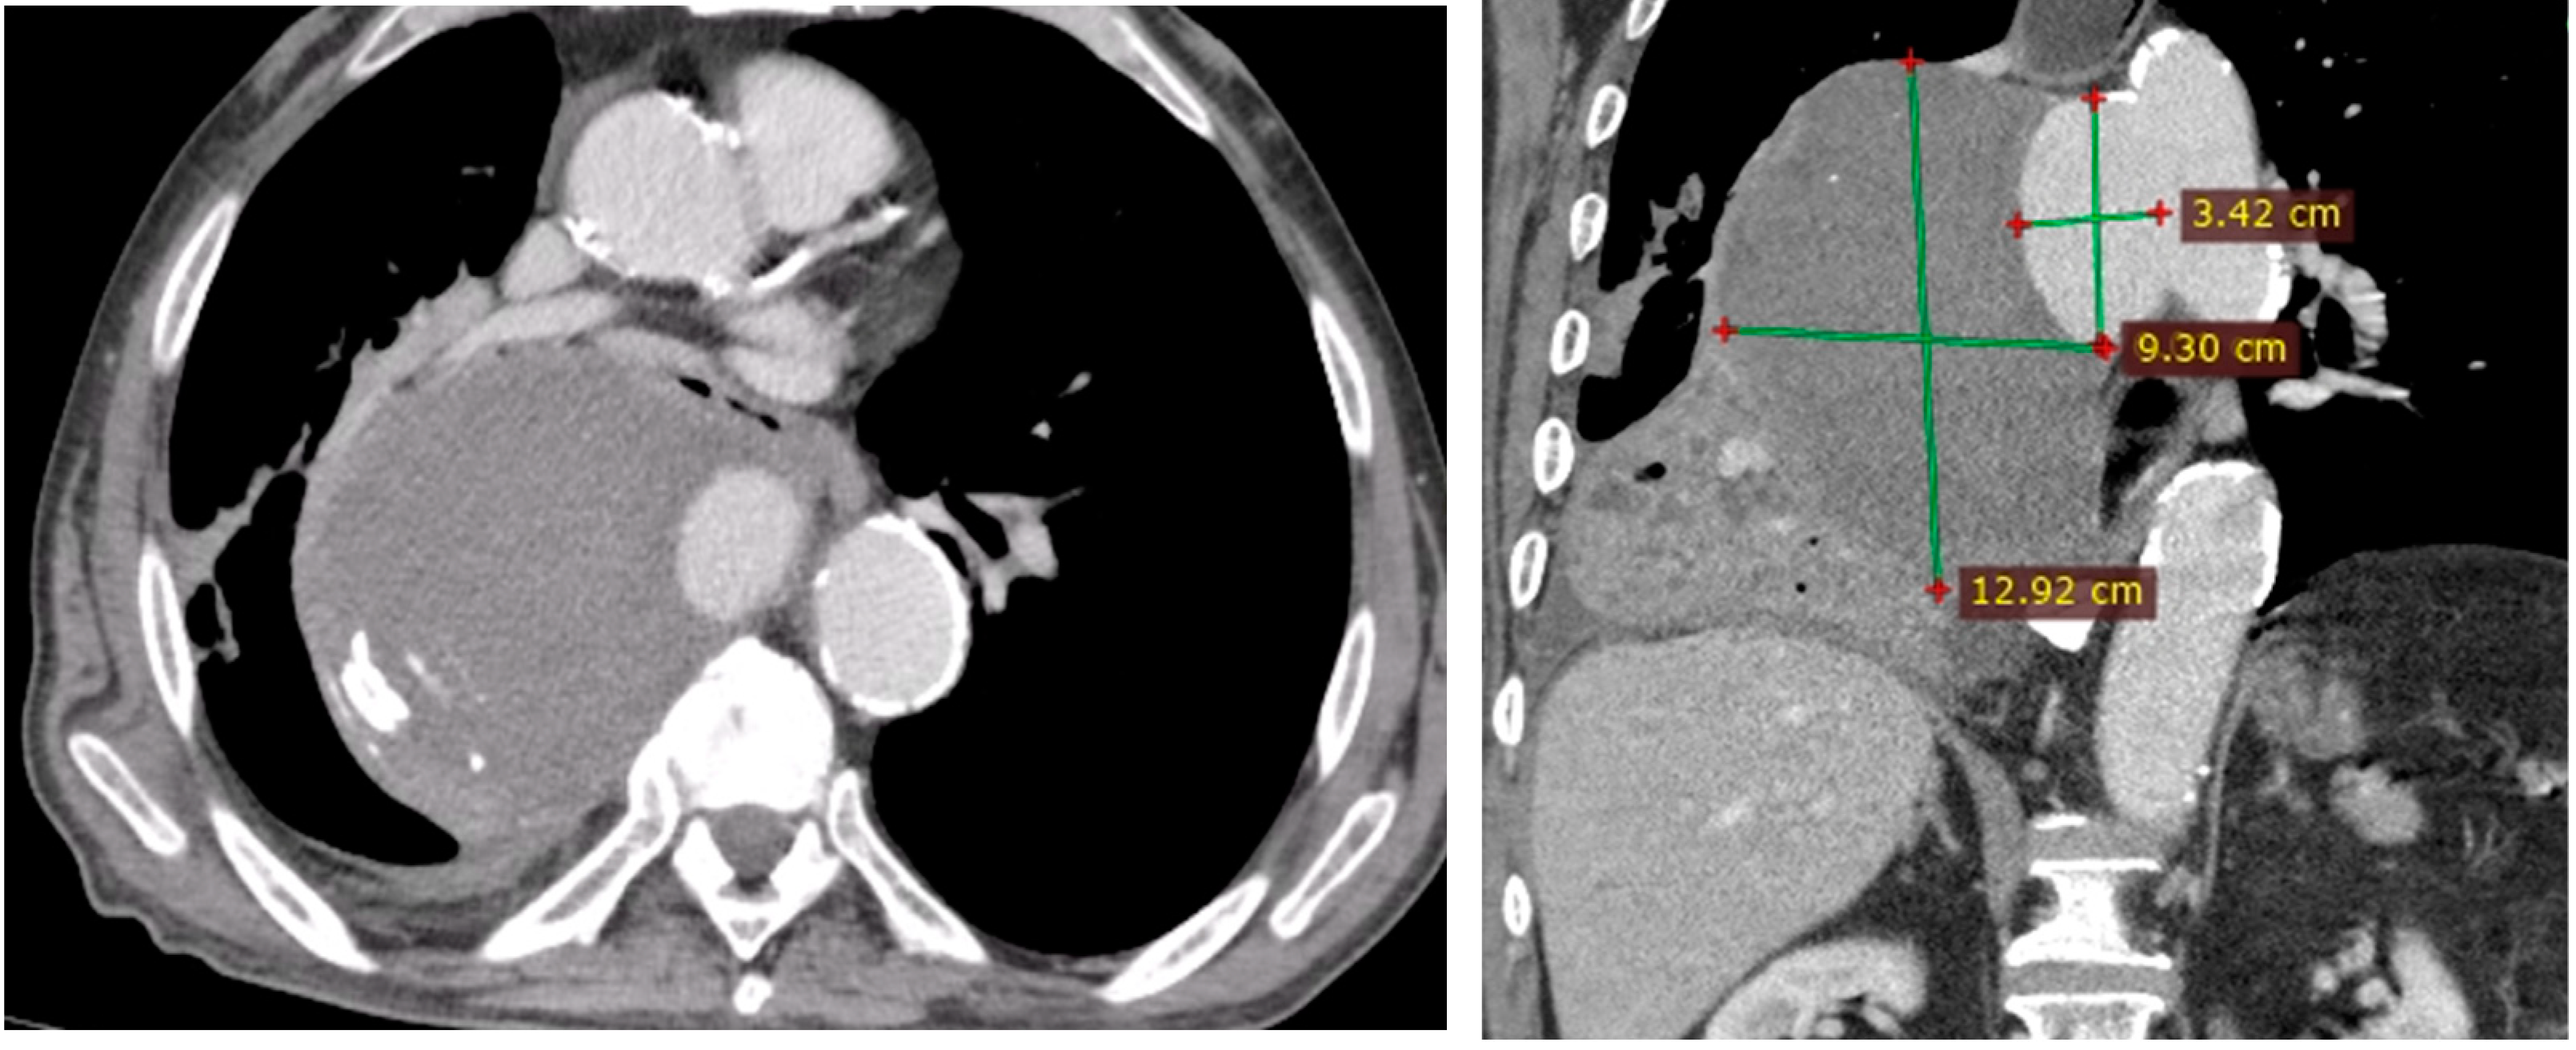

- Penetrating aortic ulcer ruptured: As seen in Figure 2, the thoracic angio-CT scan identified a penetrating ulcer within the aortic wall, particularly located in the isthmic region, measuring approximately 4.2 cm × 3.5 cm. This was a concealed source of significant concern, as it posed an imminent risk of catastrophic hemorrhage.

Figure 2. PAU and the false aneurysm. - Right pleural aortic false aneurysm (Figure 3): The most striking feature was the presence of an expansive false aneurysm within the right pleural cavity, measuring approximately 12.92 cm × 9.3 cm. The size and location of this pseudoaneurysm were unprecedented, introducing a challenge in terms of diagnosis and intervention.

Figure 3. Right pleural aortic false aneurysm. - Megaesophagus: Notably, the imaging findings also uncovered a megaesophagus, a condition characterized by significant dilation of the esophagus. Although not the primary focus of intervention, its presence added another layer of complexity to the clinical scenario. The etiology of the megaesophagus remained to be elucidated.

- Compression of the lung: The false aneurysm within the right pleura had exerted a significant mass effect, resulting in the compression of surrounding structures, notably the lung. This compression had led to compromised ventilation of the lung, contributing to a concerning clinical picture.

- Potential lung infection (Empyema): The compromised lung, in part due to the mass effect of the false aneurysm, exhibited signs of infection. Imaging suggested the possible development of empyema. This provided a plausible explanation for the patient’s presenting symptom of hemoptysis.